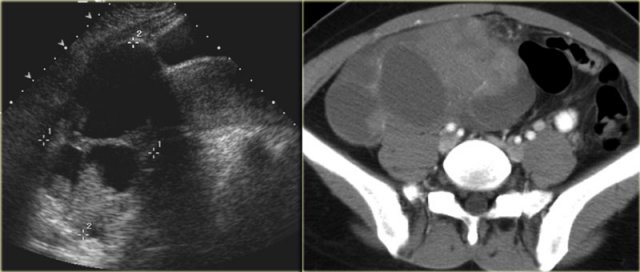

Hemorrhagic ovarian cyst Hemorrhagic ovarian cyst

The ultrasound images show multiple simple and one complex right ovarian lesion (red arrow).

The latter demonstrates diffuse low-level echos and no flow on Doppler.

Note that there is a good through transmission (blue arrow).

These findings indicate the presence of a hemorrhagic cyst.